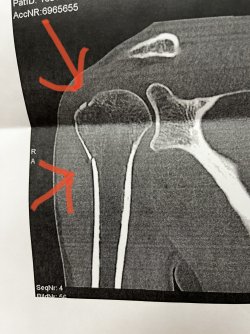

Lyckades med konststycket att få en fraktur i min axel. Dvs en så kallad Non-displaced Humerus Fracture, vilket inte är helt illa. Men jag skulle vilja veta om någon har haft en liknande, och vad för typ av slinga, axellås eller liknande ni fick?

Jag blir behandlad utomlands, och dom vill att jag skall ha 6 veckor i ett låst läge, dvs en sån där 45 graders utstickande grunkemoj. Se bild...

Är det din fraktur på bilden?

I sådana fall är det en avlösning av tuberculum majus, vilket är en benknöl där ett par av rotatorcuff-musklerna fäster. Anledningen att du har ett låst läge på din behandling är för att du inte får abducera i axelleden, dvs ej föra armen utåt med muskelkraft -det skulle kunna medföra att benbiten sticker iväg och med påtagliga följdbesvär. Olika förband eller ortoser finns för att uppnå detta. I ditt fall är att undvika aktiv abduktion av stort värde.

Såg nu att ditt ’förband’ har 45-grader ut från kroppen. I Sverige brukar man ha immobilisering intill kroppen men med nåt i armhålan. Men kan inte så mkt om ditt förband, så låter det vara osagt. Men rekommenderar att du söker vård när du är hemma i Sverige igen

Japp, det är min fraktur :) Enligt läkaren så ligger det bra på plats. också efter en vecka med bara slinga. Så jag tänker att I motsatts mot vad läkaren säger, så borde det kunna gå att läka, även utan 45 graders vinkeladapter.. Men jag vet ju så klart inte.